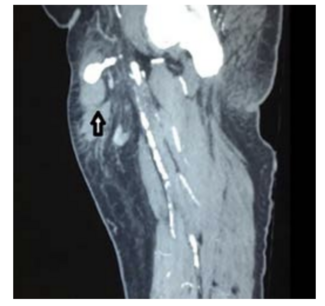

The authors describe a pseudoaneurysm in 2013 that was managed by compression of the neck of the pseudoaneurysm.